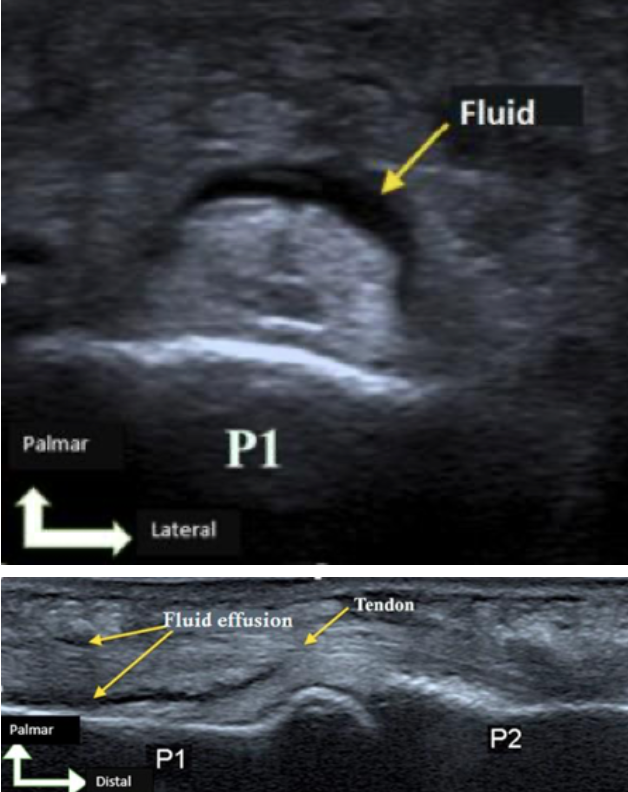

Point-of-care ultrasound in the emergency room may also assist in diagnosis of tenosynovitis. The patient’s hand can be fully immersed in water while a high-frequency linear transducer is used to visualize the affected digit. Concerning findings include peritendinous effusion (see figures) on the transverse or longitudinal views, or thickening of the tendon sheath visualized on ultrasound. The contralateral hand can be used as a control to account for any anatomy variability.

A prospective study in 2018 by Jardin et al identified 57 patients who had suspected flexor tenosynovitis and found that ultrasound demonstrated 94% sensitivity in diagnosis of flexor tenosynovitis.

US findings in Flexor Tenosynovitis